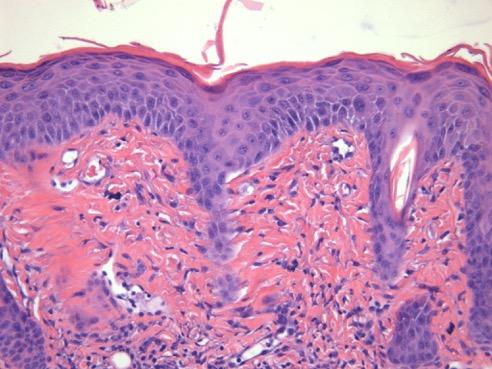

Psoriasis is well-known for causing too many skin cells on elbows, knees, and across the body, but people living with psoriasis may also be at an increased risk of heart disease. Effects of overactive immune cells in the skin can spread system-wide and inflame arteries, causing heart attacks and strokes. Treatment of psoriasis and its deadly comorbidities costs an estimated $135 billion annually in the United States, and up to $26,000 per patient, according to the National Psoriasis Foundation. For the 1 in 50 people worldwide living with psoriasis, there is an urgent need to understand how painful, thickened skin can lead to such fatal complications.